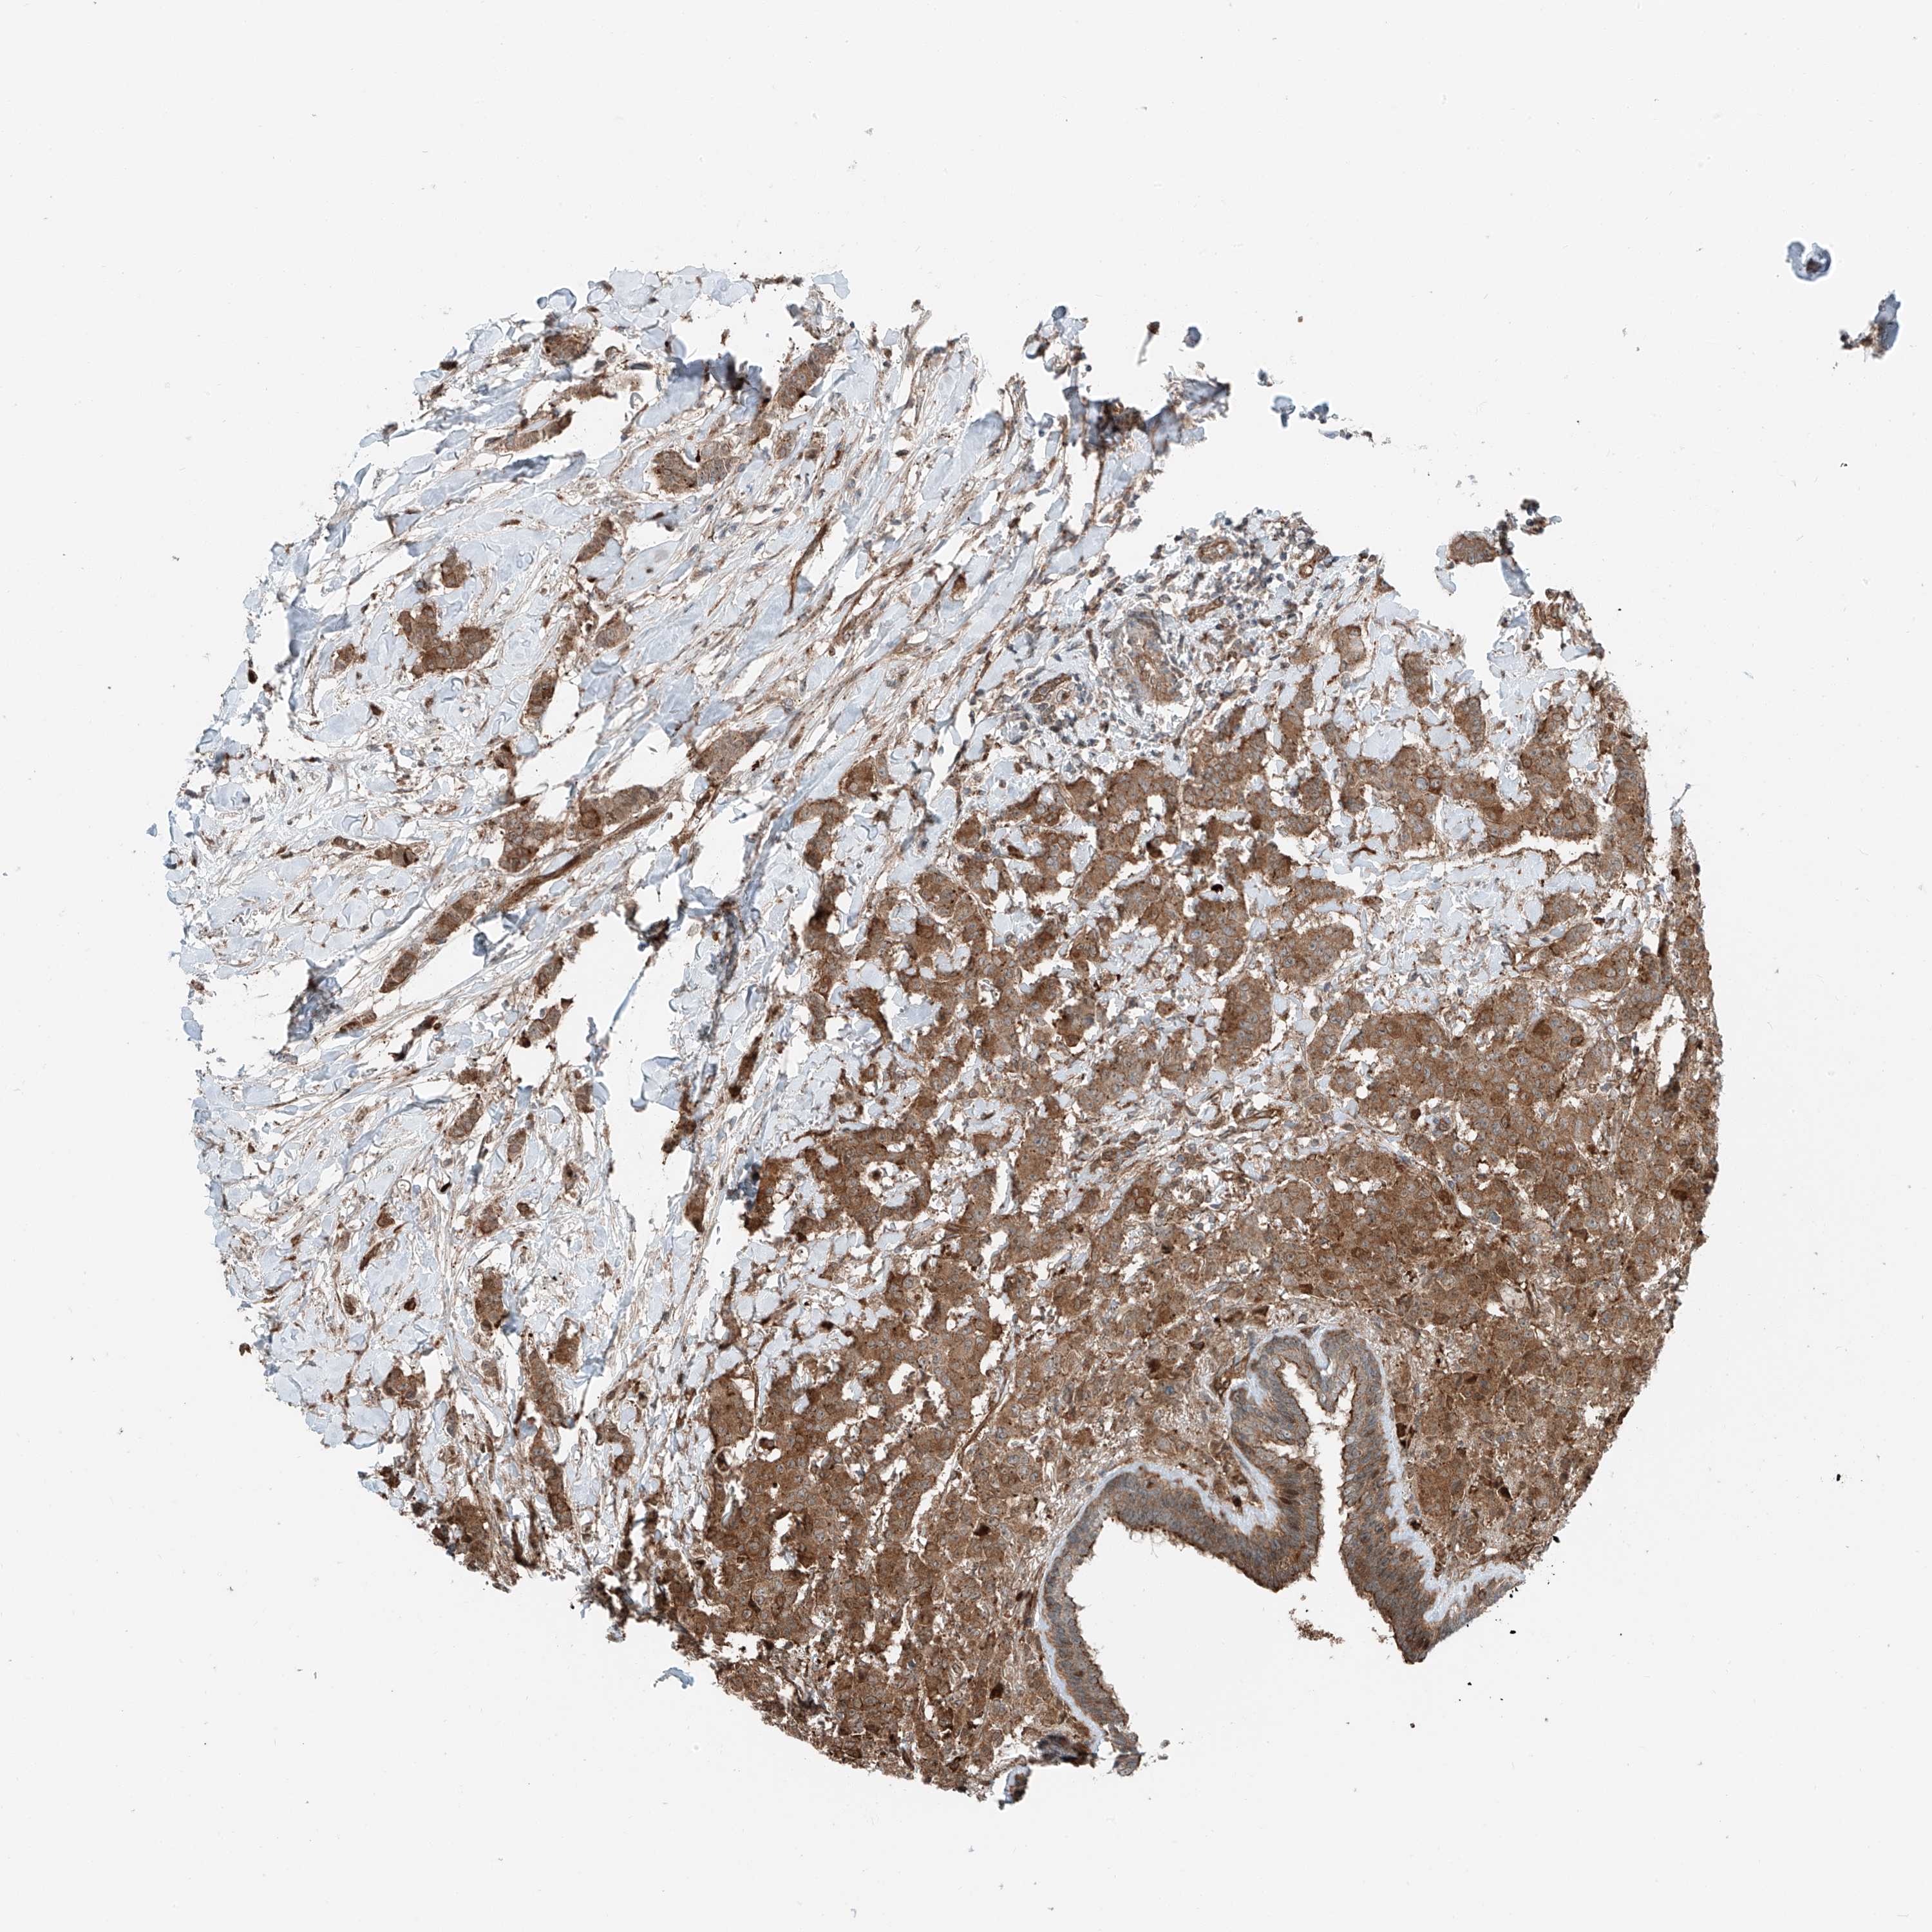

CANCER BREAST CANCER Show tissue menu

BRCA TCGA BRCA VALIDATION PROTEIN EXPRESSION